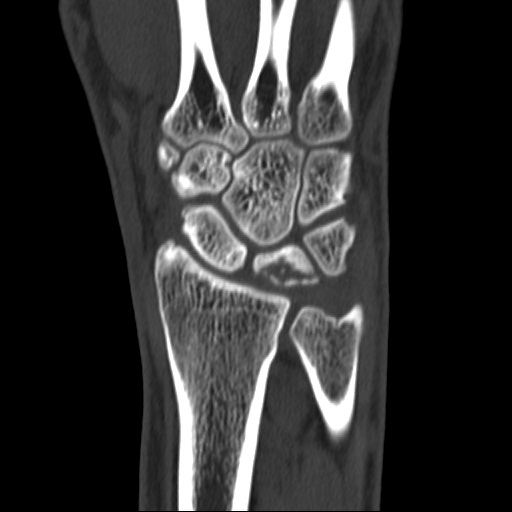

키엔벡병 수술 전

2021.06.12